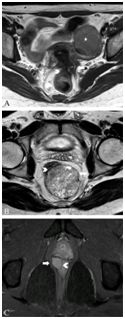

肿瘤复发通常在术后2年,MRI是显示复发、盆腔播散和淋巴结转移的金标准(图16、17),圆形或突出的损害边缘提示肿瘤复发,直角边缘提示纤维化。术后并发症,如吻合口漏、出血、瘘和盆腔脓肿与积液(图18),钆增强图像具有诊断作用,不过检测上述并发症时CT优于MRI。

图16  75岁男性直肠癌复发,放化疗后8个月轴位T2加权像显示直肠腔内真菌样肿物(长箭头),伴骶骨前软组织复发且累及骶骨(箭头)。

图17  41岁男性直肠癌腹会阴(AP)切除术后1年复发。A.轴位T2加权像显示右侧盆壁复发肿瘤为锯齿状软组织影(长箭头),可见骶前疤痕(箭头)。B.冠状T1加权钆增强像显示复发肿瘤增强(长箭头),右侧阴部神经周围侵犯(箭头);C.轴位T1加权钆增强像显示右侧阴部管的阴部神经周围侵犯(长箭头)。

图18  35岁女性直肠癌放疗后。A.轴位T2加权像直肠右侧肿物(箭头),右侧直肠系膜内脓肿(长箭头),脓腔内见碎片和低密度信号气泡;B.轴位T1加权钆增强像显示直肠肿瘤增强(箭头),直肠系膜右侧脓肿边缘增强(长箭头)。